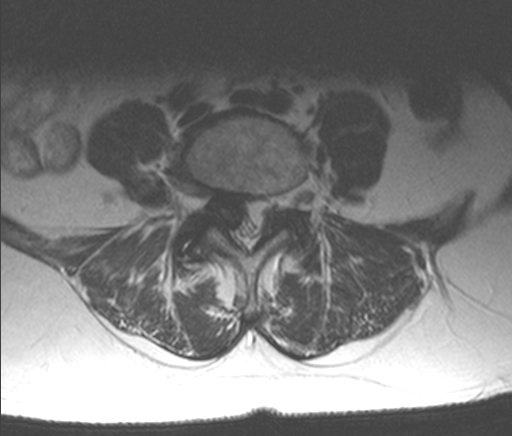

Advertisement - Members don't see this ad Yup. My disk is bigger than yours. Go post in pic thread. No tumor, infection, or hematoma. Its all disk baby.

lobelsteve Full Member Staff member Volunteer Staff Lifetime Donor Verified Member Verified Expert 20+ Year Member Gold Donor Joined May 30, 2005 Messages 23,646 Reaction score 15,256 Points 8,731 Location Canton GA Website www.stevenlobel.com Attending Physician Apr 14, 2015 #3 Mad Jack said: My disc is so big I can't even walk anymore. Click to expand... Not even close. No extrusion or anything.

emd123 Full Member 10+ Year Member Joined Feb 25, 2010 Messages 4,263 Reaction score 1,563 Points 5,356 Attending Physician Apr 14, 2015 #7 101N said: I've had about a dozen cauda equina's in my career. One a few years ago had a canal back out in the axials. Click to expand... I've seen a few cauda equinas, too (not quite 12). That's c3/4, though.

P pmrmd Full Member Lifetime Donor Verified Member 15+ Year Member Gold Donor Joined Mar 22, 2008 Messages 4,130 Reaction score 2,742 Points 6,851 Location Phoenix, Arizona Attending Physician Apr 14, 2015 #8 Its C4-5 bro

S SSdoc33 Full Member 15+ Year Member Joined Apr 23, 2007 Messages 15,466 Reaction score 8,067 Points 7,616 Attending Physician Apr 15, 2015 #10 i think this is a disc. could be a z-joint cyst.

emd123 Full Member 10+ Year Member Joined Feb 25, 2010 Messages 4,263 Reaction score 1,563 Points 5,356 Attending Physician Apr 15, 2015 #11 SSdoc33 said: View attachment 191213 View attachment 191214 i think this is a disc. could be a z-joint cyst. Click to expand... I agree with z joint cyst but need more images

F fentanyl patch Full Member 15+ Year Member Joined Feb 4, 2010 Messages 53 Reaction score 6 Points 4,611 Attending Physician Apr 15, 2015 #12 emd123 said: I agree with z joint cyst but need more images Click to expand... Nice picture. Looks like a disc to me. Large facet cysts I've seen are usually hyperintense.